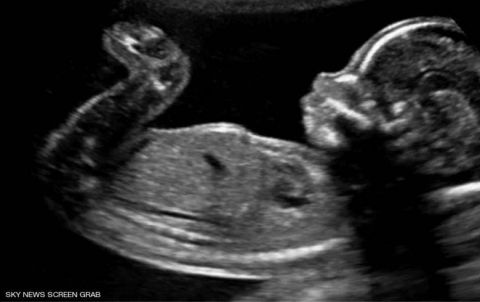

لا يتذكر الناس شيئا عما فعلوه حين كانوا في أرحام أمهاتهم، لكن باحثين في الطب كشفوا عدة أمور يقوم بها...